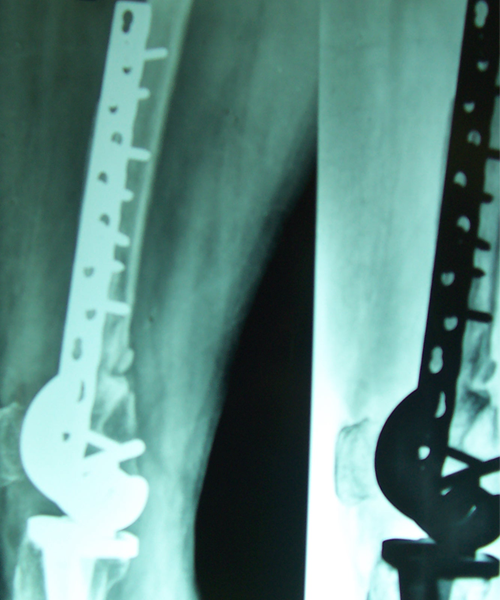

Case:14 Periprosthetic Fracture

60 years old patient with total knee replacement on left knee presented with open grade 1 injury. Debridement & slab given on emergency bases. Fixation with plate & screws done. Union was seen after 6 months.

Pre-Op AP

Pre-Op Lat.

Immdiate Post-op

1 and half months Post-op

2 and half months Post-op

3 and half months Post-op

4 and half months Lateral

6 Years Follow-Up